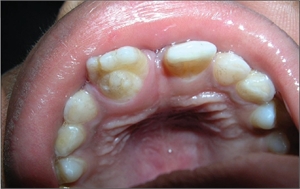

A broad spectrum of morphological variations is attributed to it. Typical signs of dens invaginatus deep include the infolding of enamel and dentine from the foramen caecum or even the tip of the tooth cusps. In some cases, the infolding may extend to the roots. This condition most affects the maxillary lateral incisors though other dentition may also be prone.

As detection of this dental condition might be rather tricky. Dentists would sometimes use methylene blue dye to observe abnormalities in the dental fissures indicating the infolding of dental enamel. Clinical identification of the invagination entrance can be difficult as entrances can be unremarkable and be similar to natural fissures.